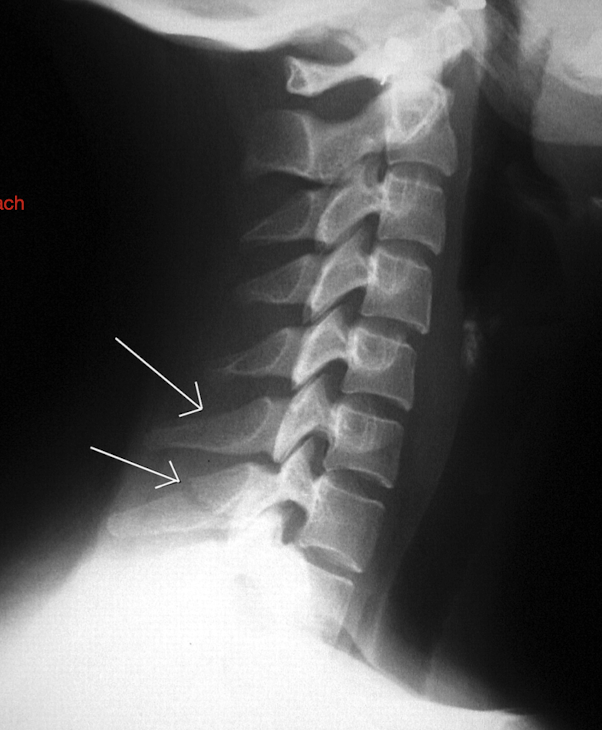

Label these 4 Lines? (C/S)

Notice: Post Vertebrae Intact, Ant Vertebrae w Fx